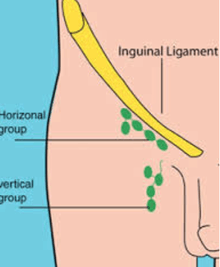

An Inguinal lymph node is a type of lymph node in the inguinal region. It can refer to:

A view of the different inguinal lymph nodes

- Superficial inguinal lymph nodes

- inferior -inferior of the saphenous opening of the leg, receive drainage from lower legs

- superolateral - on the side of the saphenous opening, receive drainage from the side buttocks and the lower abdominal wall.

- superomedial - located at the middle of the saphenous opening, take drainage from the perineum and outer genitalia.[1]

- Deep inguinal lymph nodes

- arranged near and along the femoral vein of the leg.

- drain the deep parts of the lower limbs, women's clitorus, and men's penis

- connected to the superficial lymph nodes and send their drainage to those via lymph vessels.[2]